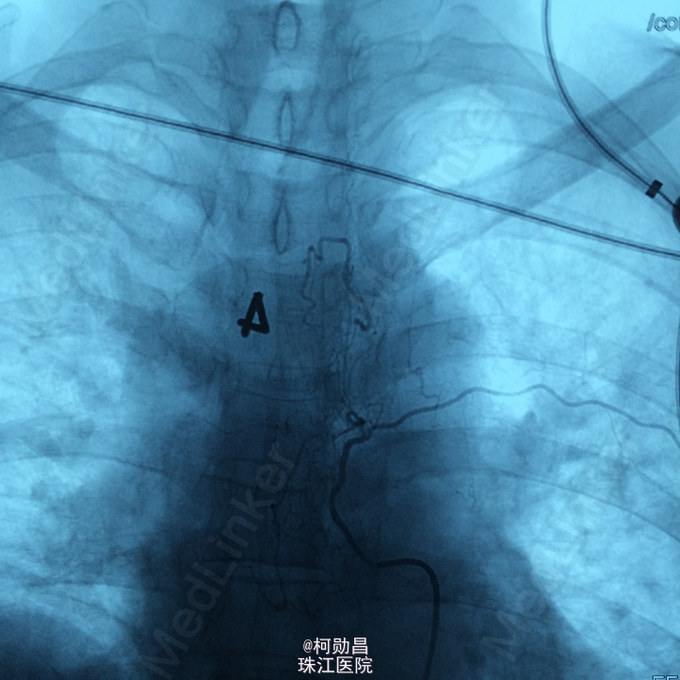

查体:痉挛性截瘫,肌力 4/5 级,马鞍区感觉减退,肛门括约肌张力下降, 腱反射活跃。 辅助检查:腰椎穿刺脑脊液检查示脑脊液蛋白 53mg/dL,葡萄糖 59mg/dL,细胞学检查可见成熟的淋巴细胞,寡克隆区带阴性,免疫球蛋白 IgG 指数为 0.58。布氏杆菌、梅毒、脑脊液 / 血清血管紧张素转换酶水平、结核杆菌聚合酶链反应、单纯疱疹病毒、EB 病毒、水痘 - 带状疱疹病毒,包柔螺旋体(莱姆病)血清学检测均为阴性。结合患者的脊髓 MRI 表现,初步诊断为脊髓血管畸形

诊断:硬脊膜动静脉瘘 处理:予全麻下行栓塞治疗,选择予 withn-butyle-2-cyanoacrylate(医用胶)完全闭塞 。